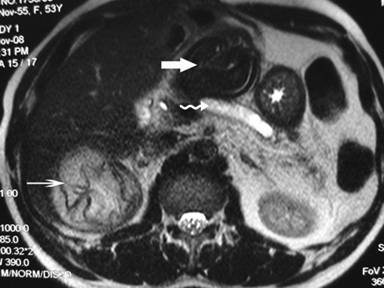

Plain X-ray of the abdomen revealed classical curvilinear calcification in only one patient with a hydatid cyst in the pancreatic body (Figure 1). Ultrasonographic examination which recorded the site, size and extent of the lesions, documented the cystic lesions as anechoic rounded structures in all cases. An abdominal CT scan documented the cysts as spherical hypodense space-occupying lesions. All the lesions were solitary, measuring 26-50 mm in diameter (mean 36.7 mm). Five lesions were cystic with thin walls and one lesion appeared as a multiseptated cyst. Magnetic resonance imaging for defining the lesion and its relationship with the pancreatic duct was performed in three patients (two lesions in the head and one in the body of the pancreas). Two lesions were located in the head (Figure 2, 3, 4, 5), two in the body (Figures 6 and 7) and two in the tail region of the pancreas (Figure 8). In two cases, a preoperative diagnosis was possible due to the presence of classical features which also included a concomitant hydatid cyst in the liver in one patient. All patients underwent surgical exploration; intraoperative cyst puncture for aspiration cytology was successful in three cases (two cases with cysts in the head and one case with a cyst in the body of the pancreas); the results of cytological examination were positive in all cases. A fragmented laminated membrane was observed in two patients, scoliosis in three and hooklets in one patient (Figure 9). The laminated membrane was seen as a foliated, acellular, pale, eosinophilic structure which stained strongly positive with periodic acid Schiff staining and negative with alcyan blue staining. The hooklets had a characteristic shape presenting as a blade, a guard and a root. They were not stained with Papanicolaou stains and their appearance was enhanced by turning down the microscope condenser. There were no complications after diagnostic aspiration. In all three cases, the aspirated fluid was colorless and contained a mean sodium level of 128 mEq/L (range: 128-130 mEq/L), chloride level of 69 mEq/L (range: 65-70 mEq/L) and potassium level of 5.8 mEq/L (range: 5.4-6.3 mEq/L). Cysts in the distal pancreas observed in the two patients were treated by a distal pancreatectomy with splenectomy. Cysts in the body were treated by a pericystectomy in one patient (Figure 10) and a central pancreatectomy in another patient. Cysts in the head region in two patients were treated with evacuation, partial cystectomy and tube drainage of the cavity after protecting the surgical area with a scolicidal solution (Figure 11). Both patients underwent T-tube drainage of the common bile duct; there was rapid regression of the jaundice in these patients. The T-tube cholangiogram confirmed the free flow of bile into the duodenum; the tubes were eventually removed in the third postoperative week. Postoperative confirmation of the hydatid cysts was obtained on the basis of the histopathological findings. There were no postoperative complications; all patients recovered uneventfully. The antihelminthic drug, albendazole, was administered postoperatively (10 mg/kg body weight/day) in all cases for a period of 6 months. All the patients were followed up at three-month intervals and each patient underwent clinical examination, abdominal ultrasonography and indirect hemagglutination tests; no patient had cyst recurrence or dissemination. The mean follow-up time was 58.7 months (range: 4-120 months).

Figure 4. Contrast-enhanced computed tomography scan of the abdomen demonstrating a solitary cystic lesion (50 mm) in the pancreatic head. Note the distended gall bladder (Patient #6). |

Figure 5. T-weighted magnetic resonance image in the same patient demonstrating high signal intensity due to the cystic lesion in the head of the pancreas with an obstructed biliary ductal system (Patient #6). |